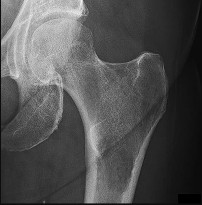

Question 2

A 28-year-old male sustains a high-energy Pauwels type III femoral neck fracture.

Compared to a Pauwels type I fracture, which of the following biomechanical forces is most significantly increased at the fracture site?

Explanation

The Pauwels classification of femoral neck fractures is based on the angle of the fracture line relative to the horizontal plane. A type III fracture has an angle greater than 50 degrees, making it more vertically oriented. This vertical orientation significantly increases shear forces across the fracture site, leading to a higher risk of varus collapse, nonunion, and fixation failure.